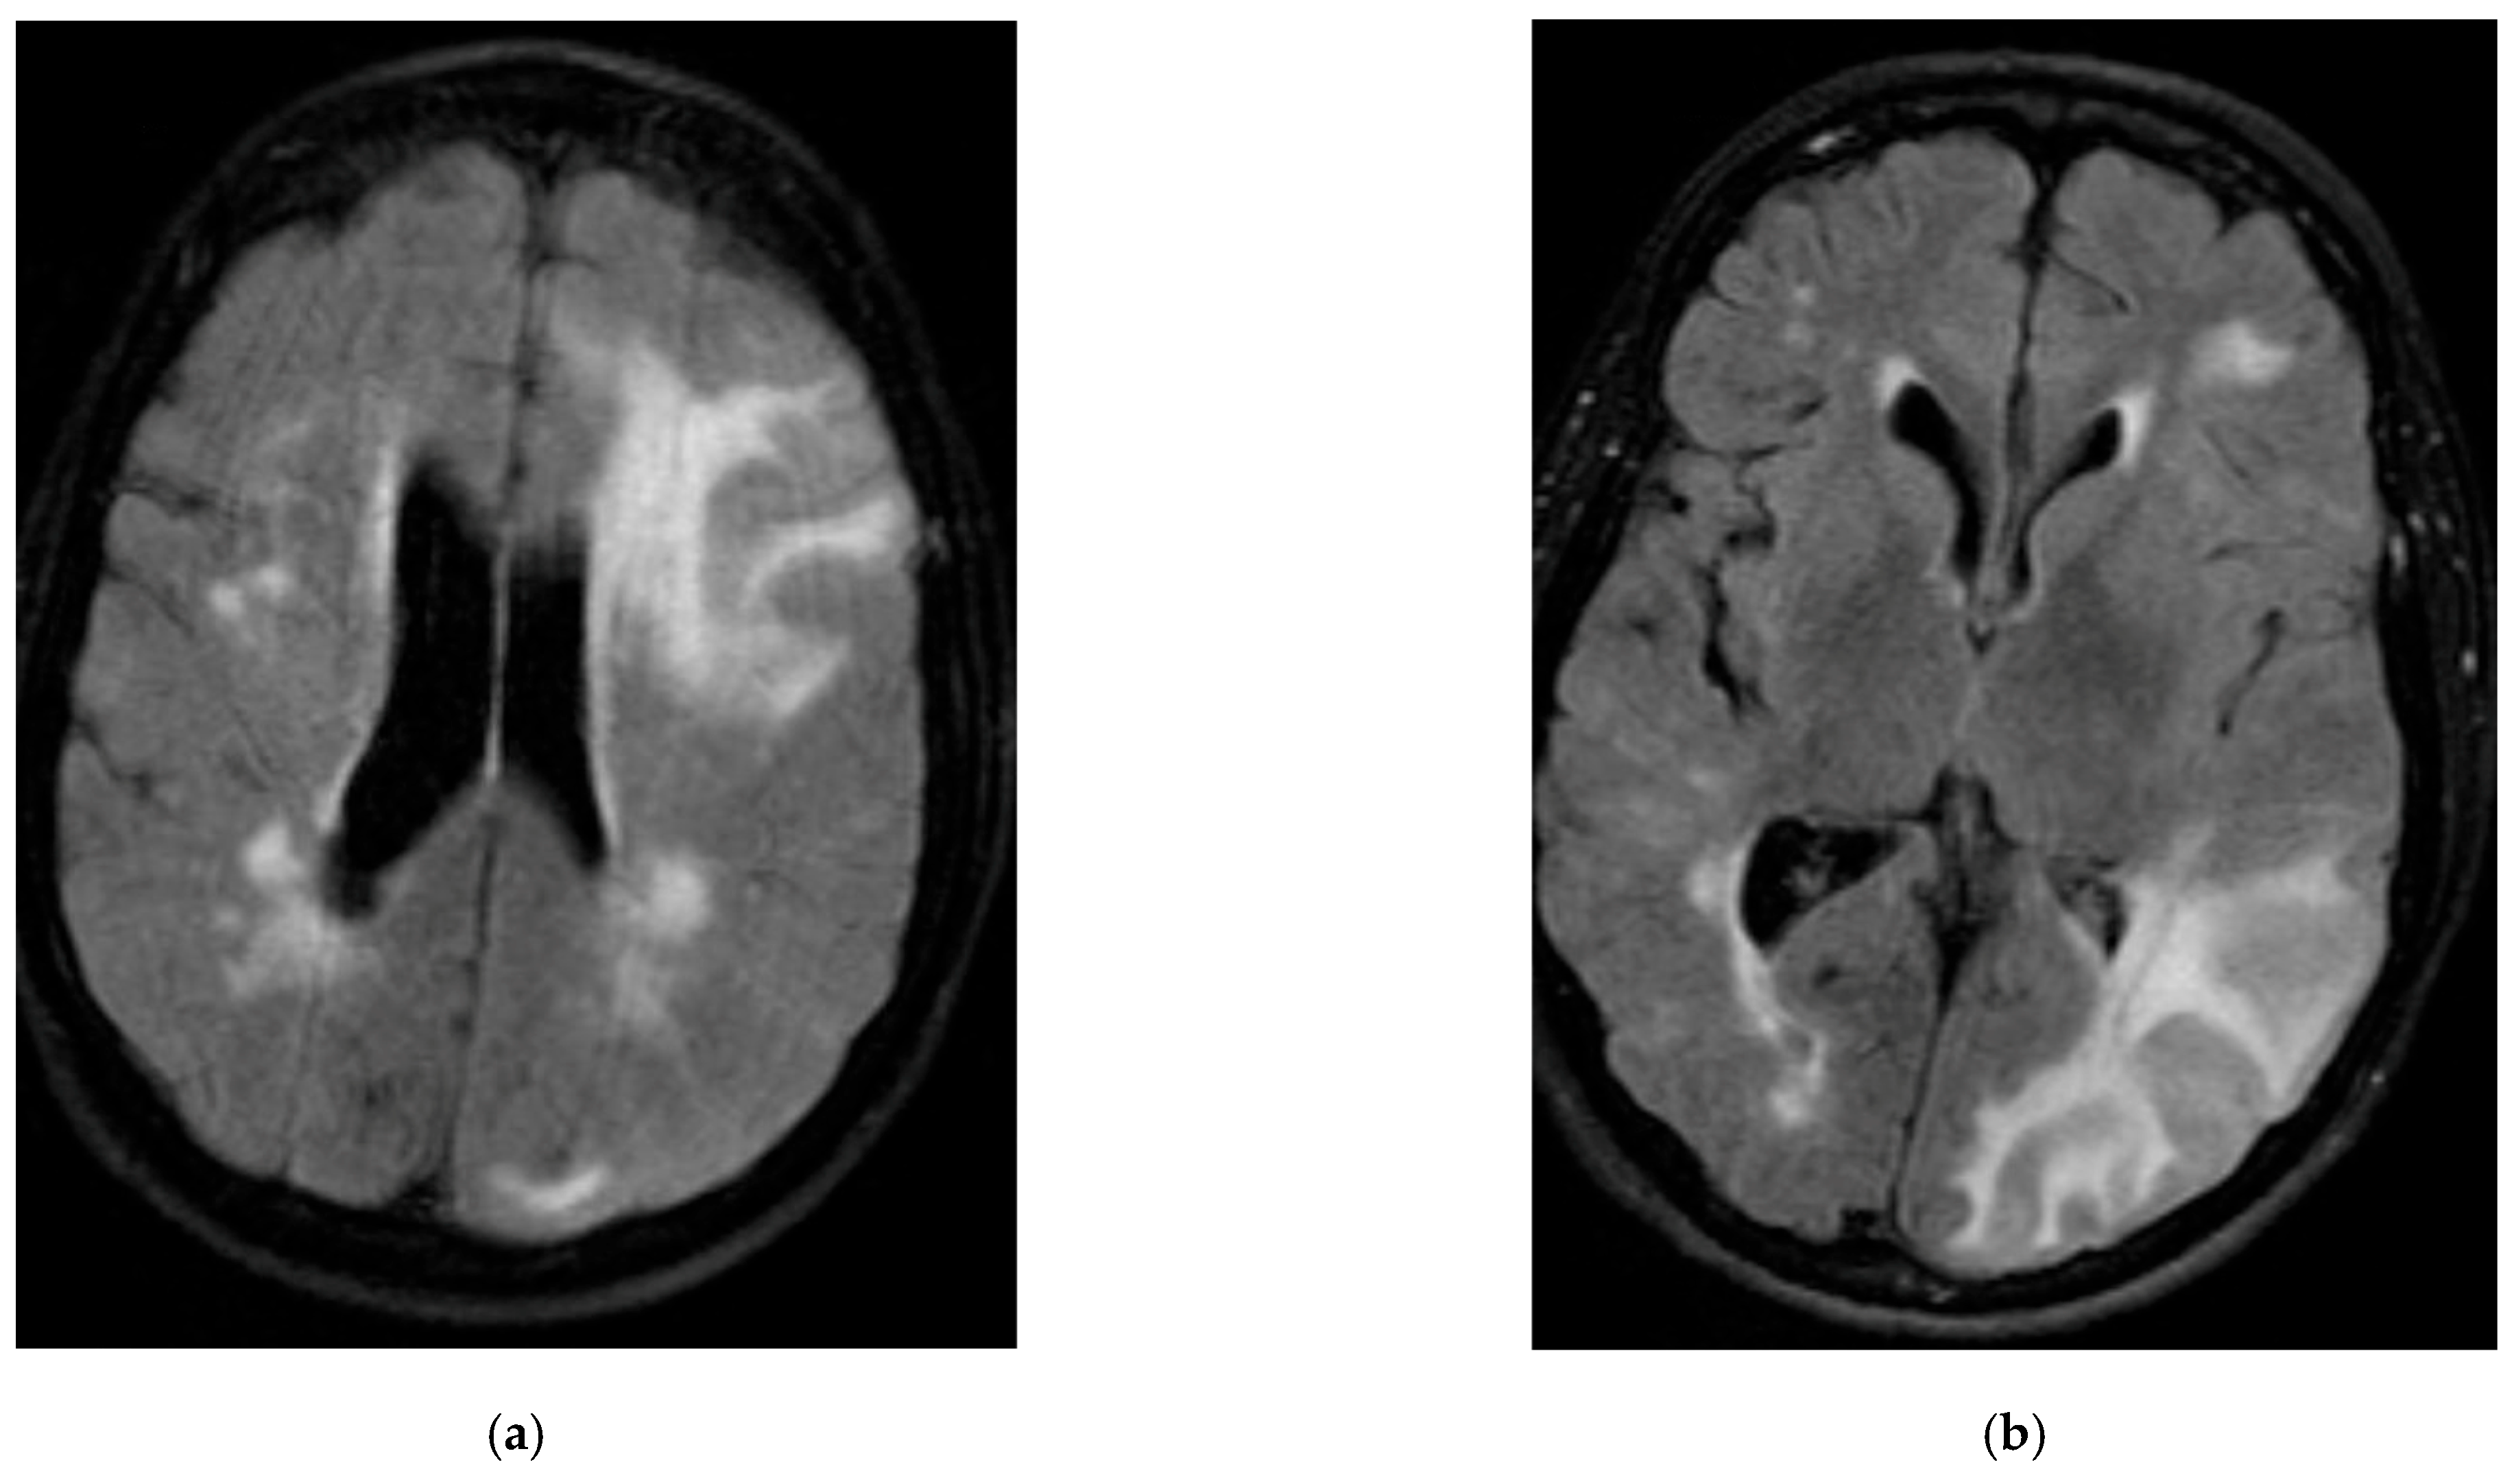

2. Case Summaries

2.1. Patient 1

2.2. Patient 2

2.3. Patient 3